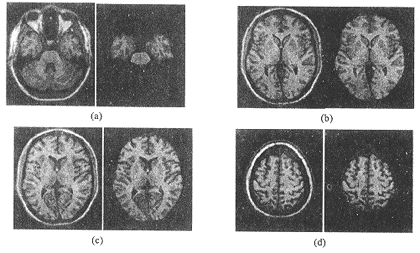

图5为3D MR图像中几个不同的轴向层面图及提取的有关大脑部分的显示。可以看出,该方法对于颅骨、头皮及皮下脂肪能够较容易地去除,而与大脑连接较紧密的小脑去除难度相对大些。要实现全自动和更为准确的提取,还需要进一步的研究。

图 5 从颅底到颅顶的几个不同层面处理前后的对比。各图中,左部是原图,右部是提取结果

(a) 原图包含较多的非脑组织,处理后只保留端脑和桥脑;(b) 小脑被很好地去除;

(c)、(d) 原图靠近颅中与颅顶,成分较简单,处理中去除了颅骨、头皮及脂肪。